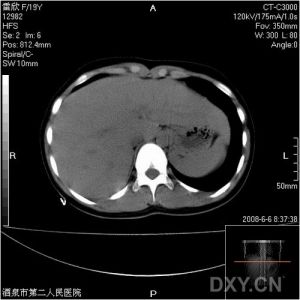

急腹症正確的治療依賴於正確的診斷,而正確的診斷又依賴於全面的收集病史資料及進行多方面的檢查。影像檢查是臨床檢查方法之一。隨著新型X線診斷機的套用及造影技術的不斷改進和更新,它在疾病診斷中的地位也不斷提高。在急腹症的診斷中也是如此。例如:發現膈下游離氣體,結合臨床表現對診斷腹部空腔臟器穿孔有決定性意義。腹部影像中出現擴張的腸管積液平面,應當首先考慮是否存在腸梗阻。值得提出的是影像檢查不僅是一項重要的診斷方法,而且對某些急腹症,如套迭的治療也有著重要的作用。因此,提高醫務人員的診療水平,就需要X線醫生與臨床醫生的密切配合,才能達到一個高質量的診斷標準。

一般急腹症利用腹部平片或透視即可作出診斷,但對一些非典型患者,處於急性期、慢性期的病人,可以針對性的選用一些特殊檢查(如CT、MR等)。